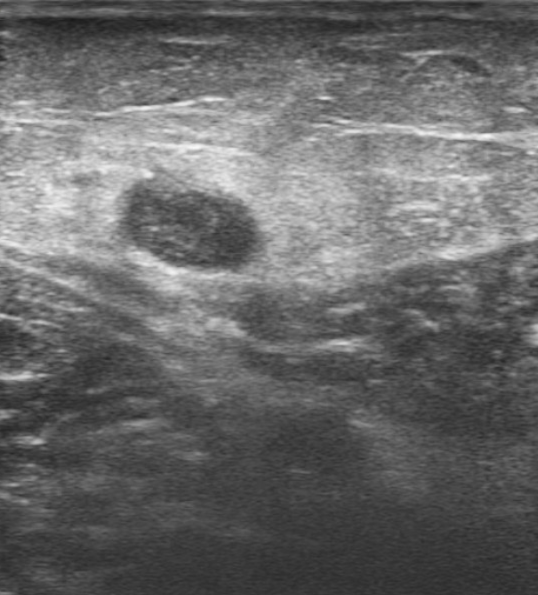

Ecografía de miembro inferior izquierdo: contenido hiperecogénico en todo el trayecto de la vena safena interna, no compresible. Sistema venoso profundo permeable sin datos de TVP (Imagen 2,3,4).